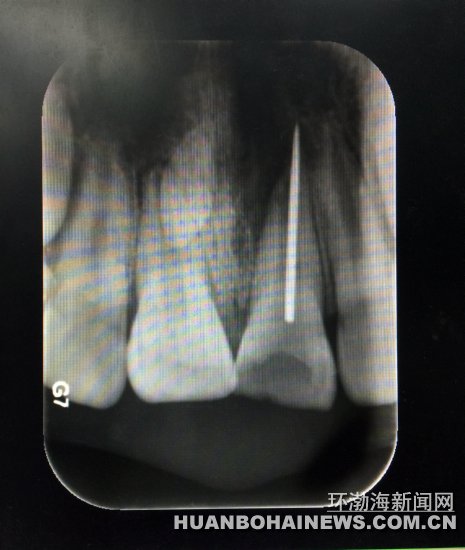

X光片顯示縫衣針扎入牙齒根管。 醫(yī)生取出的縫衣針。 近日,9歲的淘淘(化名)在玩耍時誤將縫衣針扎入門牙根管中,市協(xié)和醫(yī)院口腔醫(yī)院醫(yī)生利用顯微鏡下根管異物取出術(shù),從這名熊

X光片顯示縫衣針扎入牙齒根管。X光片顯示縫衣針扎入牙齒根管。

該院牙體二科任宏宇醫(yī)生接診后,結(jié)合牙片發(fā)現(xiàn)這名小男孩左上門牙根管里扎有一根斷針。孩子牙齦紅腫疼痛,煩躁不安,家長十分著急。

淘淘說,自己拿著媽媽的縫衣針給門牙里的牙洞“撓癢癢”,可玩著玩著針就斷了,半截針扎進了門牙里。醫(yī)生隨即施以顯微鏡下根管異物取出術(shù)。10幾分鐘后,一根2厘米左右的斷針從孩子的左上門牙根管里順利取出。原來,孩子嘴里這顆扎進斷針的牙齒是有齲洞的齲齒,孩子玩針時才誤將鋼針扎進牙的根管里。